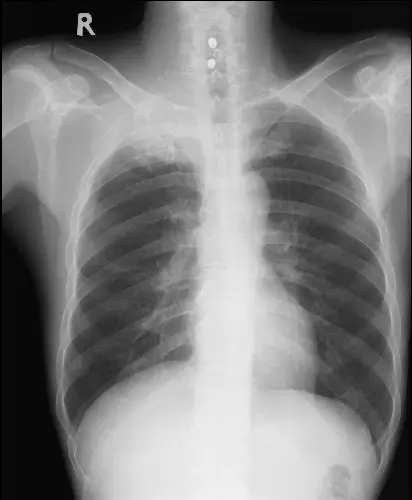

51 歲男性病患,因為近半年來右上背酸痛和右上肢麻痹和無力到院就醫。他因這些病症在他院接受止痛藥物治療和手術治療頸椎椎間盤突出開刀,但症狀未見改善。到院前三個月,他開始出現右眼皮下垂和視力模糊。他過去抽菸,一天一包達三十年之久。到院胸部 X光和電腦斷層檢查如圖。多次痰液微生物顯微鏡檢和培養均為陰性。以下何者是最有可能的診斷? 圖片 圖片

影像一:胸部 X 光(PA 正面)

胸部 X 光顯示右側肺尖(right lung apex)區域可見不對稱性密度增高影(apical opacity),呈現均質的軟組織密度陰影,位於右側鎖骨上方的 superior sulcus 區域。相較於左側乾淨的肺尖,右側明顯有胸膜增厚或軟組織腫塊影,此發現高度懷疑肺尖部腫瘤(apical cap / superior sulcus mass)。右側肋骨及鎖骨骨質是否有破壞需進一步 CT 評估。